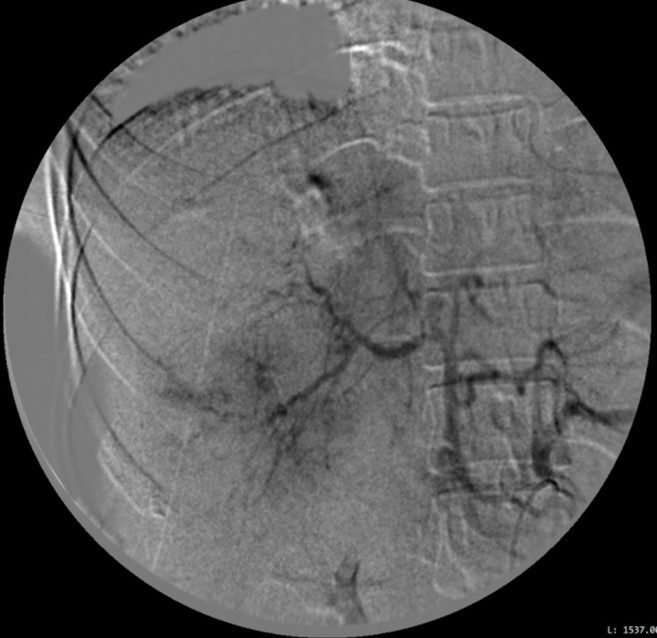

Bênh nhân được can thiệp nội mạch lúc 1:00 sáng ngày 03/04/2021. Chụp động mạch gan chung thấy ổ xuất huyết hoạt tính từ nhánh HPT VIII và nghi ngờ ở HPT VI, tương ứng với các vùng khuyết tưới máu. Chọn lọc nhánh HPT VIII bằng microcatheter, nút mạch bằng gelfoam. Chọn lọc nhánh HPT VI, nút mạch theo kinh nghiệm (empiric embolization) bằng gelfoam.

Hình 3. Chụp mạch chọn lọc nhánh HPT VIII thấy ổ xuất huyết hoạt tính (mũi tên), nút mạch bằng gelfoam. Nút mạch theo kinh nghiệm nhánh HPT VI.